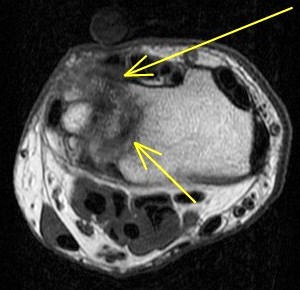

Ulnar impingement syndrome